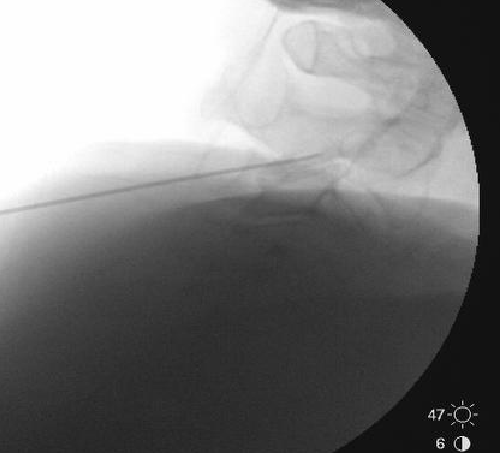

Only thing I do differently is aim for a touch more posterior placement of the needle. I try to make sure the very tip of the needle is at but not beyond the x in the image below. I also take a final lateral right before RFA. I think it helps reduce the frequency of neuritis to be a bit more posterior.

View attachment 395708

I appreciate the input, but I'm using a 10mm active tip and I'm burning quite a bit of MBN in that pic right there. Going more posterior theoretically means I'm getting less of it.

I think there is a very substantial cutaneous aspect to these nerves.

Based on some discussion on here a few years back, I tried burning 1/2 way along the pillar rather than anterior edge, but felt like I saw an immediate increase in neuritis. I suspect there are at least 2 different causes. Some neuritis comes from burning nerves with a sensory input to the skin, unavoidable, but some comes from being a little off target and only irritating rather than completely burning a medial branch nerve.